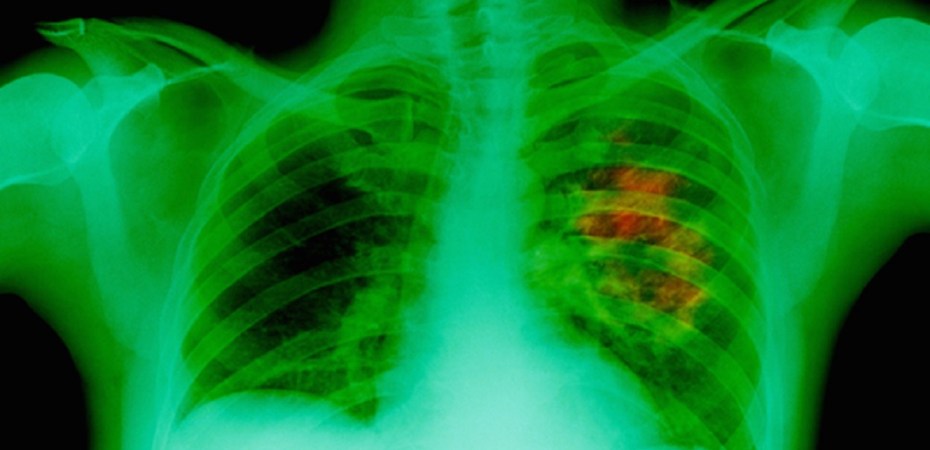

Tobacco is Legal, but Cannabis Actually Kills and Prevents Lung Cancer

Contrary to our previous understanding, it turns out that cannabis can stop and even prevent lung cancer, according to scientists from the American Association of or Cancer Research. In 2007 the association produced a report demonstrating that the psycho-active ingredient in cannabis, Delta-tetrahydrocannabinol (THC), “cuts tumor growth in common lung cancer in half and significantly reduces the ability of the cancer to spread.”

This is worth repeating: cannabis can stop lung cancer. Furthermore, Dr. Donald Tashkin, professor emeritus of medicine at UCLA, points out that while tar from cannabis smoke has a higher concentration of cancer-causing materials than tobacco smoke, there seems to be no correlation between inhalation of cannabis smoke into the lungs and the development of lung cancer, which is the opposite for tobacco.

Another important finding regarding the effect of cannabis on pulmonary health is that there appears to be no causal link between smoking cannabis and the onset of chronic obstructive pulmonary disease (COPD), a “collection of lung diseases including chronic bronchitis, emphysema and chronic obstructive airways disease.” COPD is the most common cause of death from tobacco smoke.

Decades of pulmonary research is in: pot decreases the risk of lung cancer and does not cause chronic obstructive pulmonary disease (COPD), and, it is an effective treatment for many types of cancer, including lung cancer. Without question, tobacco smoking is dangerous to lung health and can cause cancer, yet cannabis remains stigmatized by public perception and the law.